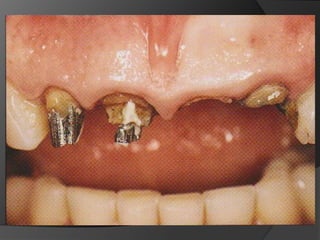

Planificación Del Tratamiento En Restauraciones UnitariasRestauraciones Extracoronarias

Estructura coronaria insuficiente para retener la restauración dentro de la corona del dienteEstructura dentaria defectuosa o socavadaModificar los contornos para mejorar la oclusión o la estética

CORONA DE RECUBRIMIENTO PARCIAL: Corona de deja una o más superficies axiales sin cubrir. Proporciona retención moderada.

CORONA COMPLETA EN METAL: 	En dientes con múltiples superficies axiales defectuosas o destruidas. Proporciona la máxima retención.	La superficie oclusal	favorece  el chequeo oclusal

CORONA COMPLETA METAL-CERÁMICA: Iguales indicaciones que la metálica pero  estética

CORONA TOTALMENTE CERÁMICA: Combinación de recubrimiento completo y máxima estética. La eliminación de estructura dentaria es mayor.